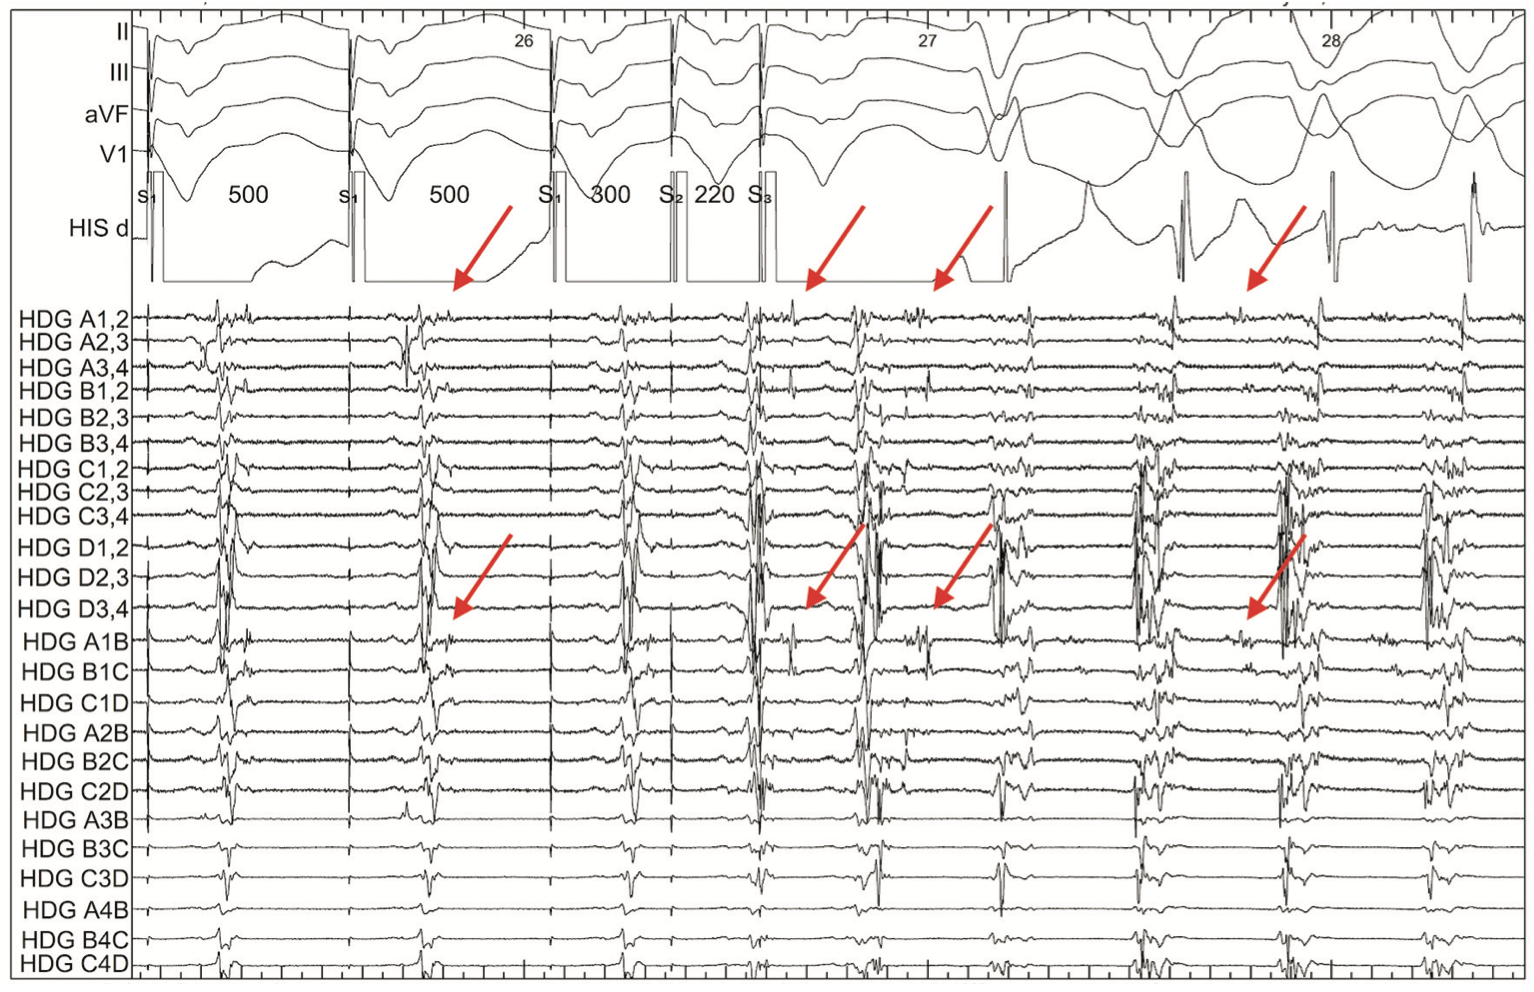

The Advisor HD Grid was then placed back in the epicardium in an area of interesting LPs while induction was attempted. VT was induced with double ventricular extrastimuli at 500-300-220. Using the Advisor HD Grid, an activation map was created of this right bundle/right superior axis VT with a tachycardia cycle length of 360 ms. Analysis of the induction of VT showed the interesting LP decrement during ventricular extrastimuli. Identification of these decrement evoked potentials (DEEP) has been demonstrated to be more specific for a critical isthmus than LP-only mapping.11,12 In this example, the decremental signals then become mid-diastolic signals during VT, revealing the critical isthmus within limited mapping during this hemodynamically unstable VT (Figure 6). Signals such as these are the essence of substrate mapping for VT.